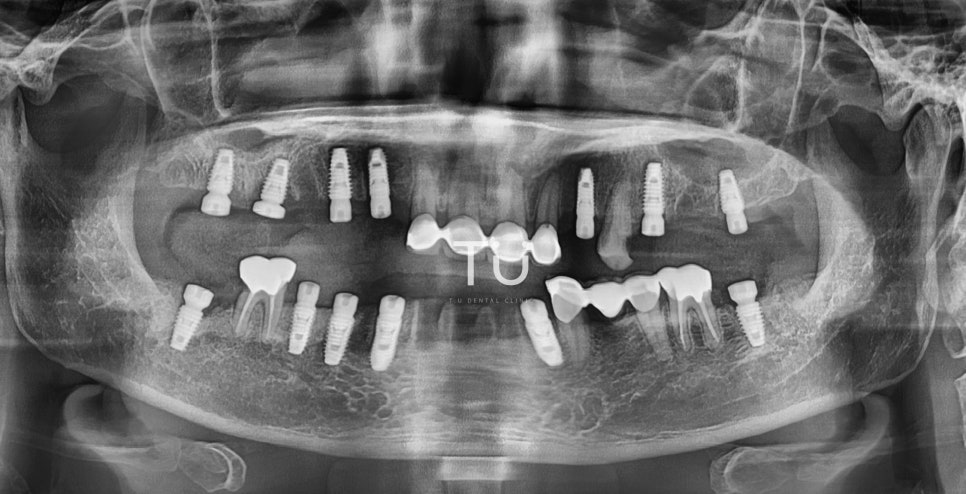

After

(픽스쳐 식립 후)

임플란트의 뿌리라고 할 수 있는

픽스쳐(fixture) 를 식립한 후의 모습입니다.

전반적으로 구치부의 식립이 많이 이루어졌죠.